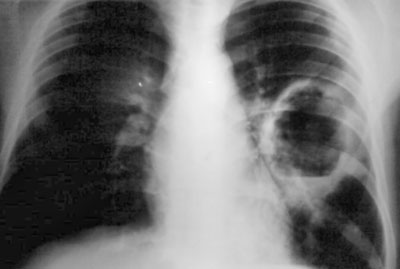

Откашливание гнойной мокроты приводит к облегчению состояния больного. Обусловлено это восстановлением проходимости бронхов. Часто это сопровождается неприятным запахом изо рта. В стадию преддеструкции рентгенологическое исследование часто является малоинформативным. При деструкции удается выявить очаг гнойного воспаления. Очень тяжелым течением характеризуется гнойной лобит. При этом страдает целая доля одного или обоих легких. У детей при лобите ярко выражен интоксикационный синдром, и выявляются признаки острой дыхательной недостаточности (боль в груди, цианоз, тахикардия). В детском возрасте выше вероятность вовлечения в процесс плевры. При воспалении плевры образуется жидкий экссудат. Затем развивается гнойно-фиброзная стадия. Исходом гнойного плеврита является хроническая эмпиема плевры.

При исследовании мокроты определяется вид возбудителя, оценивается содержание атипичных клеток, волокон, жирных кислот. Для исключения туберкулеза может проводиться проба Манту или Диаскинтест. Выявить воспаление и деструкцию тканей легкого можно при помощи рентгенографии. Альтернативным методом диагностики является томография. Немаловажное значение имеет физикальное исследование. При перкуссии определяется тупой звук. При выслушивании легких удается выявить ослабление дыхания, наличие хрипов (при обструкции бронхов). В ходе внешнего осмотра выявляется деформация грудной клетки, отставание в акте дыхания пораженной стороны грудной клетки.